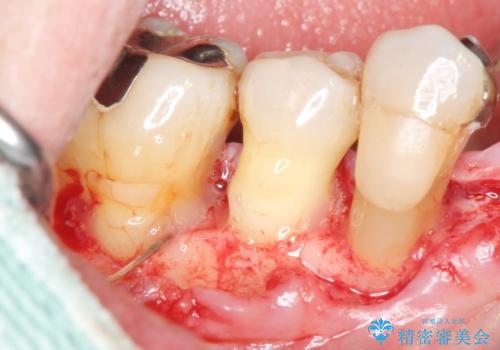

再生療法から1年後、リエントリー手術により骨の再生を確認し、骨外科処置(骨を平らにして歯周ポケットの根本的な改善を図る処置)を行いました。